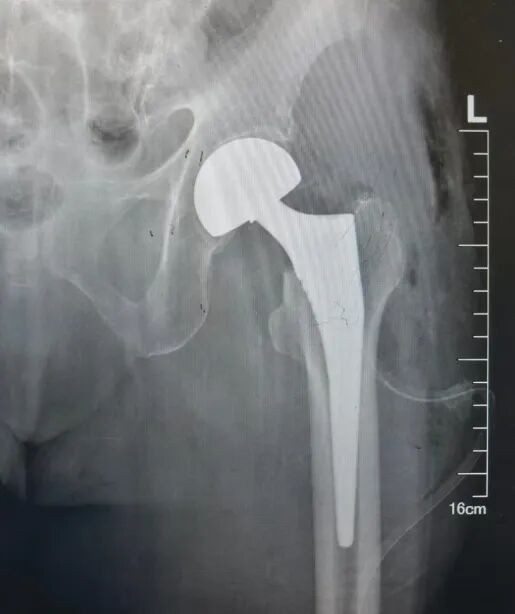

刘大诚主刀,杨效宁主任全程指导,主治医师孙一公、宋子鉴担任助手。刘大诚娴熟地将患者已经骨折的股骨头取下,然后精准选取合适的股骨头假体为患者安装。安装完成后,他仔细检查髋关节各项活动,确认关节活动不受影响、稳定性佳、匹配度良好不脱位。

器械护士贾惠清、巡回护士刘雯丽紧密配合,麻醉医师全程保驾护航。在团队的密切协作下,这台通常需要1-2小时的四级手术,仅用40分钟就顺利完成。

术后,在护士长李薇带领的护理团队精心照护下,刘奶奶恢复良好。术后第二天,她就能在辅助下逐渐开始下床活动。